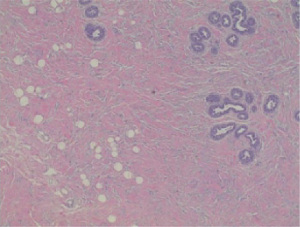

PASH is diagnosed pathologically by visualization of myofibroblasts arranged in slit-like spaces with intervening collagen (5). On ultrasound, PASH appears as a hypoechoic, circumscribed mass, similar to a fibroadenoma (6). On mammography it appears as a noncalcified, circumscribed mass, also similar to a fibroadenoma (6). On physical exam, most cases of PASH present with a palpable firm mass; rarely does it present as a diffuse, infiltrative process resulting in bilateral breast hypertrophy (7) such as our case. Observation or surgical excision is the recommended treatment (8). We present a case of bilateral PASH in a 12-year-old female and our surgical treatment in accordance with the CARE reporting checklist (available at https://abs.amegroups.com/article/view/10.21037/abs-25-46/rc).

Two months later, the patient returned to the clinic with expansive growth of the left breast, similar in appearance and timeline to the right breast (Figure 5). An ultrasound was obtained that showed a large mass encompassing all four quadrants with homogeneous echotexture and scattered cystic spaces. Given a similar presentation to the other breast, a CNB was again performed. Using a 12-gauge BARD core device under direct ultrasound visualization, 5 samples were obtained. This resulted as a juvenile fibroadenoma, which was concordant with imaging. The patient again underwent left breast excisional biopsy (Figure 6). The incision, dissection, and closure were nearly identical to her contralateral surgery. Final pathology resulted as juvenile fibroadenoma, PASH, and fibrocystic changes (Figure 7) as confirmed by two pathologists.

PASH can be seen histologically with other benign breast diagnoses, such as our patient, but could also be misdiagnosed as malignant, specifically angiosarcoma. In PASH, the visualized slit-like spaces are made up of myofibroblasts with collagen between the slits whereas in angiosarcoma, the slit-like spaces are anastomosing blood vessels (5). Immunohistochemistry (IHC) can be used to confirm PASH from angiosarcoma. PASH tumors express CD34, vimentin, and focally smooth muscle markers such as actin, desmin and bcl-2 (11). This is in contrast with angiosarcoma where endothelial markers such as CD31 and factor VIII are positive (11). IHC was not done for our patient because after discussion with staff pathologists who read our patient’s surgical pathology, none felt that IHC was necessary. Her clinical course and history were more consistent with PASH than angiosarcoma. However, in cases where there is confusion, such as a patient with a history of radiation that would raise the risk of an angiosarcoma, use of IHC could help differentiate the diagnosis.